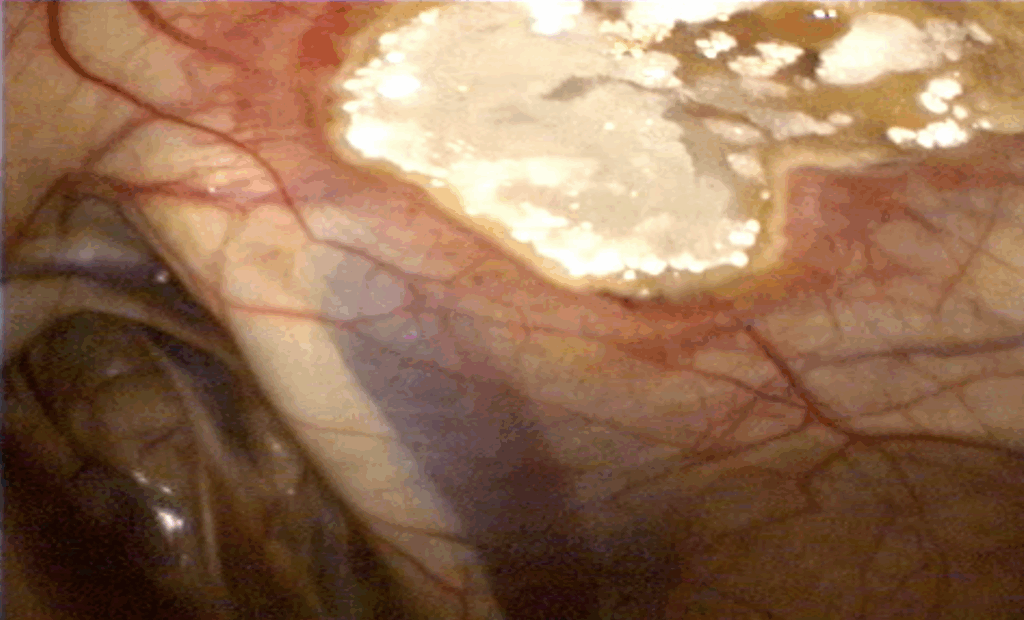

Jakmile se plíseň rodu Aspergillus uchytí ve vzdušných vacích, nalezne zde ideální místo k množení. Plísně mají rády teplo, a proto se obvykle usídlují v blízkosti velkých krevních cév, které vedou vzdušnými vaky. Tyto tepny jsou pro plísně zároveň ideálním zdrojem živin. Nejčastěji se plísně nacházejí v blízkosti vnitřní větve krkavice (obr. 3 a, b, obr. 4).